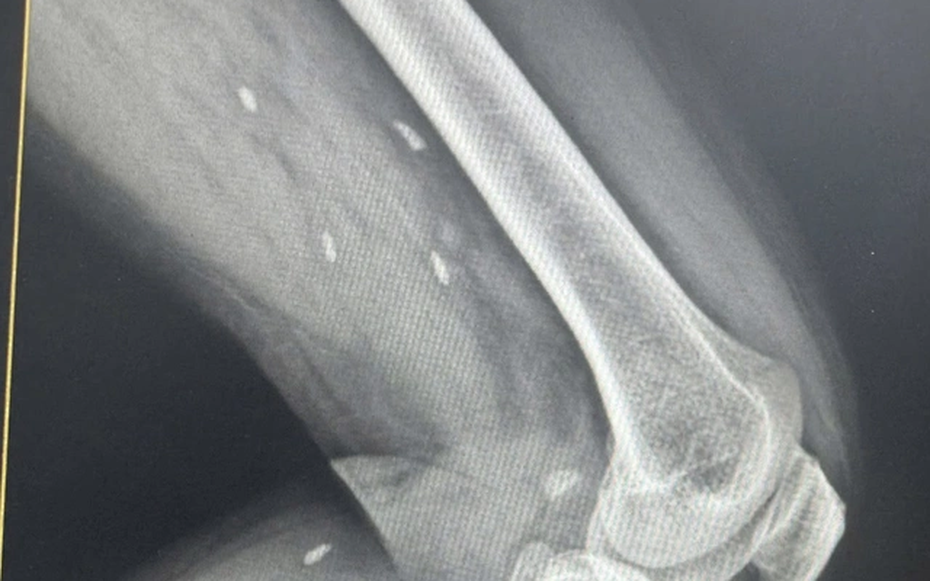

Nhiều kén sán kích thước như hạt gạo nằm rải rác ở các mô vùng xương đùi và cẳng chân bệnh nhân.

Người bệnh đến thăm khám khi có triệu chứng mệt mỏi, đau nhức nhiều ở vùng chân, lưng, hạn chế vận động… Bệnh nhân được chỉ định thực hiện chụp X- quang thường quy.

Bác sĩ Đỗ Hồng Thanh, Phó Giám đốc Trung tâm Y tế khu vực Thạch Hãn chia sẻ với Sức khỏe & Đời sống, kết quả X – quang phát hiện nhiều kén sán kích thước như hạt gạo nằm rải rác ở các mô vùng xương đùi và cẳng chân bệnh nhân.